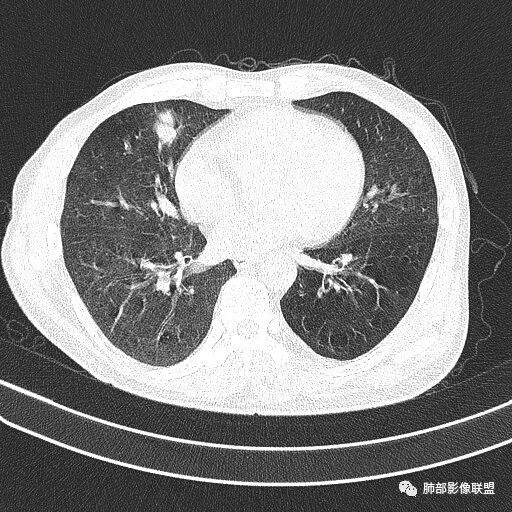

晨读病例  患者老年男性,因腰腹部疼痛3周,排尿困难1周入院。查尿常规及C反应蛋白提示泌尿系感染。肿瘤标志物NSE、细胞角蛋白19片断稍升高。胸部CT:右肺中叶内侧段类圆形肿块影,浅分叶,部分层面见深分叶,胸膜牵拉及支气管截断征象,边界清,密度低,无强化,且垮叶裂。综合考虑恶性病变,类癌及小细胞可能性大,鉴别囊肿等良性病变肺囊肿。

实性还是GGO?      实性

边界清楚、光滑?     光滑清楚,浅分叶,无明显毛刺

与支气管关系如何?   能看清楚吗

1.右肺中叶孤立不规则块影,浅分叶,未见液化或钙化,未见毛刺,未见脐凹,未见明显胸膜牵拉。

2.近肺门侧隐约见支气管截止。

3.外侧可见血管进入,病灶局部轻度强化。